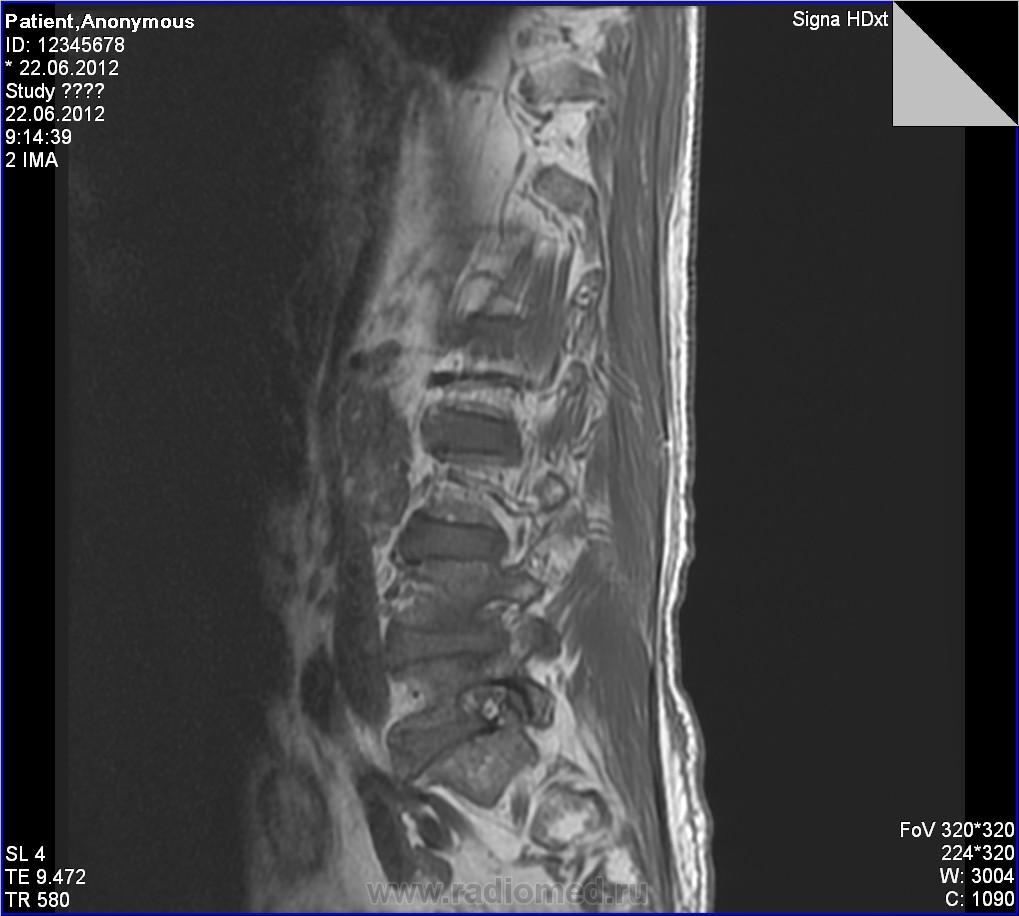

в настоящий момент я бы поставил на спондилит L5-S1 с наличием эпидурального абсцесса, преимущественным поражением L5 позвонка. Задний контур L5 разрушен, в теле L4 преимущественно отёк отёк костного мозга . Лимфоузлы (подвздошные, паракавальные, парааортальные и аортокавальные) вероятно метастатические - проверить простату обязательно, но на мой взгляд проблема с позвоночником воспалительной природы. Т2 с жироподавлением крайне желательно.

Однако и мр-сигнал от костного мозга в Т2 мне кажется тоже неоднородным (пятнистым) с гипоинтенсивными участками. Очень помог бы STIR . Не исключаю опухолевое поражение всех позвонков.

Тут нет классических остеолитических метастазов с гипоинтенсивным сигналом , мягкотканным компонентом и нечеткостью границ и тд , на которые четко можно было бы указать стрелками, зато мр-сигнал от тел позвонков снижен в виде неоднородности , или мелкоочаговости что ли... ... У человека в таком возрасте мр-сигнал наоборот должен повышаться в Т2 -ВИ , и Т1-ВИ за счет жировой дегенерации костного мозга. Думаю в последовательности с жироподавлением "светились бы все позвонки"

Случайное обнаружение соотвествующих патологических изменений в кости на рентгенограмме позволяет заподозрить рак той или иной первичной локализации. Так, известно, что литические метастазы дают рак почек, желудка, щитовидной железы, а так же большинство гематологических опухолей;

бластические метастазы характерны для рака простаты и некоторых раков легких. Смешанные литико-бластические метастазы могут давать рак молочной железы и простаты